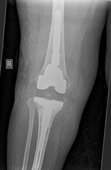

Knee replacement involves replacing the worn out knee joint. The end of the femur is resurfaced with a metallic component, a tray is placed on the tibia and a polyethylene spacer is inserted between the two components. For most total knee replacement the under surface of the kneecap is re-surfaced with a small polyethylene button.

In contrast to the hip joint the knee joint is made up of three parts or compartments. The inner (medial) and outer (lateral) halves and the patello-femoral joint (knee cap), it is possible to replace these separate components in isolation, depending of the type and pattern of arthritis the patient has.